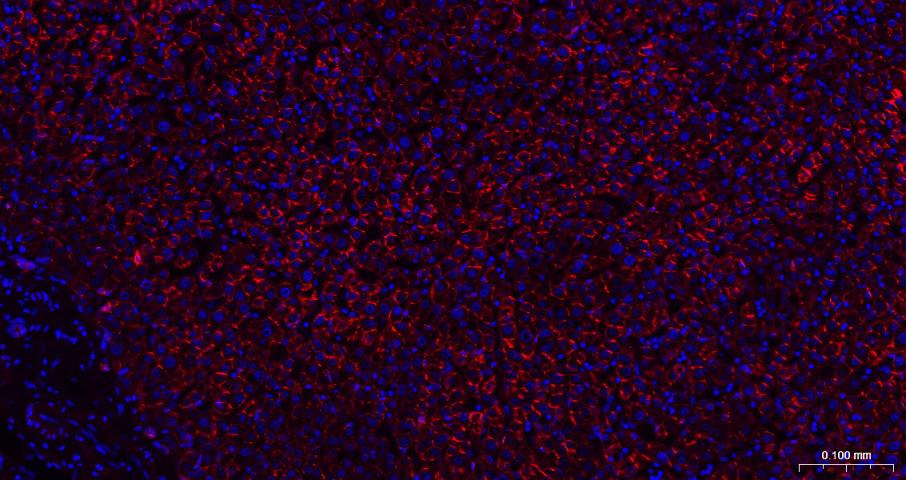

Paraformaldehyde-fixed, paraffin embedded Rat Liver; Antigen retrieval by boiling in sodium citrate buffer (pH6.0) for 15 min; The section was incubated with N Cadherin Monoclonal Antibody, Unconjugated (bsm-52389R) at 1:200 overnight at 4°C. Followed by conjugated Goat Anti-Rabbit IgG antibody (Red, bs-0295G-BF594), DAPI (blue, C02-04002) was used to stain the cell nuclei.